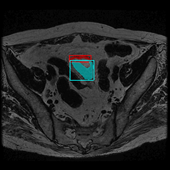

这是我在学校期间参加的一个比赛项目,项目的问题是在医学图像中准确提取膀胱边界以及对肿瘤块的识别。数据集由中国计算机大赛人工智能挑战赛提供。下图是数据集的案例,左图为原始医学图像,右图是人类医学图像专家所做的标注:

除了模型外的工作,我们还对图像数据进行了预处理,以及利用数字图像处理的一些方法进行结果提升,但这些工作由于篇幅原因省略。我讲我们模型输出结果制作了动图,具体如下,其中左边为我们挑选肿瘤面积较大的样本,右图为膀胱壁较清晰的样本,红色为膀胱壁而青色为膀胱肿瘤。